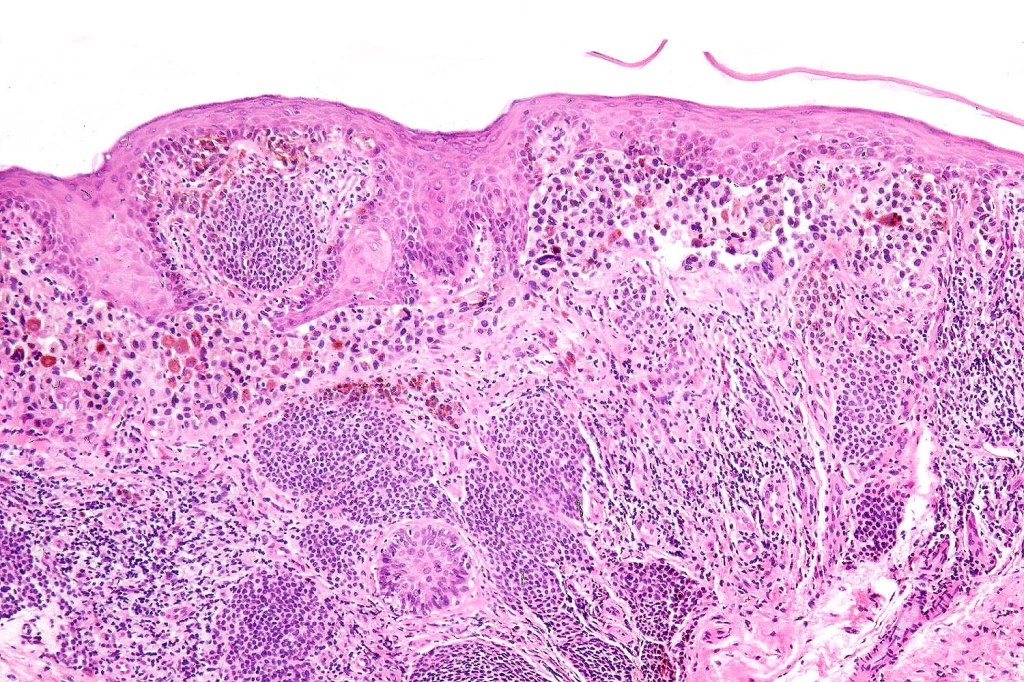

Histological features

•Junctional/compound

•Large dyscohesive nests with retraction artifact, not restricted to the tips of the epidermal ridges

•Heavy pigmentation (sometimes gray/green)

•Bridging common, often over multiple rete ridges

•Variable atypia (can be marked)

•Central pagetoid spread

•Superficial dermal atypia

•Junctional mitoses sometimes present, dermal mitoses+/-, can be multiple but never atypical

•Dermal fibrosis (sometimes lamellar)